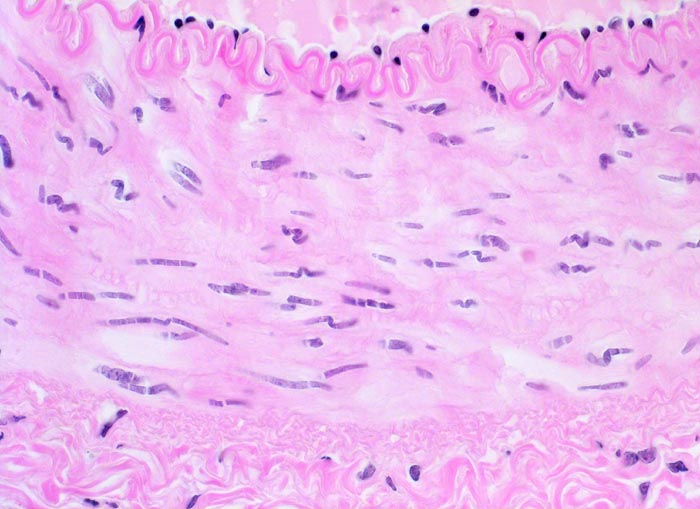

PathoPic – image database / PathoPic ID 4383 - Arterie

Arterie

Blutgefäss

Kardiovaskuläres System

Die Endothelzellen mit wenig subendothelialem Bindegewebe sitzen auf einer prominenten gewellten Lamina elastica interna. Die dünnere Lamina elastica externa ist in dieser Färbung nicht abgrenzbar. Die Kerne der glatten Muskelzellen der Media sind langgestreckt und verlaufen gewellt.

Histologie

400